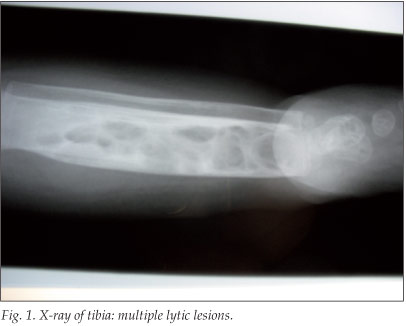

A 3-year-old HIV-infected boy first presented to our medical service at 11 months of age. He was noted to have firm, enlarged, matted axillary lymph nodes >3 cm in diameter; this was in keeping with BCG lymphadenitis of his right axilla. He also had pneumonia, oral thrush and neuro-developmental delay. He was subsequently started on highly active antiretroviral therapy (HAART). During this admission, he was diagnosed as having tuberculosis (TB), based on acid-fast bacilli (AFB)-positive gastric washings, and he was commenced on TB therapy. Owing to the presence of BCG adenitis, the systemic isolates of AFB were submitted to polymerase chain reaction (PCR) analysis and found to be Mycobacterium bovis rather than M. tuberculosis. He was discharged after 6 weeks of treatment, placed on 6 months of anti-TB treatment, and booked for regular follow-up, from which his caretakers defaulted. Almost a year later, he presented with multiple small subcutaneous abscesses evenly distributed over his trunk and limbs. Soft-tissue thickening over the tibial aspects of both lower legs was noted. Ultrasound of the abdomen revealed an enlarged spleen and liver; both revealed multiple focal hypodense lesions. The tibial thickening that had been detected clinically was not investigated further at the time. However, 2 months later he presented again with severe pain, subcutaneous inflammation and fluctuation over the anterior surface of the medial aspect of the lower legs. X-ray changes included a localised osteopenia and a periosteal reaction (Fig. 1). Surgical intervention revealed bilateral tibial osteitis. Histological examination of bone biopsies confirmed osteitis secondary to M. bovis infection. In summary, this boy developed disseminated (lymph node, cutaneous, hepatic, splenic and osteal) BCG infection subsequent to routine immunisation.